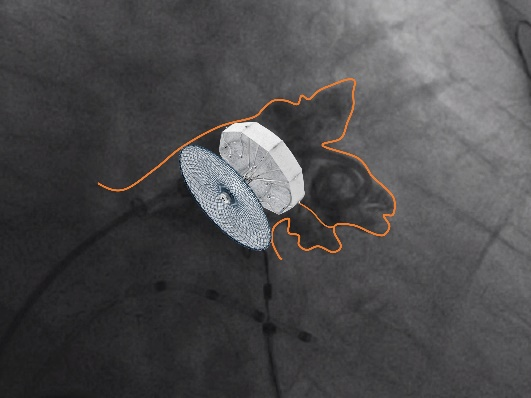

考虑到封堵的安全性和无残留,郭军教授、陈小明教授团队最终选择了LAMax LAAC®2430 Normal型号左心耳封堵器,锚定伞锚定在共干区域,封堵盘覆盖左心耳口部。

LAMax LAAC®左心耳封堵器锚定伞打开完全,锚定伞9个“J型”钩的圆头与中间Mark点接近同一个平面;封堵盘完全打开,形成“新月形”。右肩位造影检查,无残余分流

LAMax LAAC®左心耳封堵器封堵盘在DSA下牵拉15s,锚定伞稳定无移位

符合COVER原则,将LAMax LAAC®左心耳封堵器释放,再次DSA造影检查,封堵器形态无变化,封堵效果好,手术圆满完成